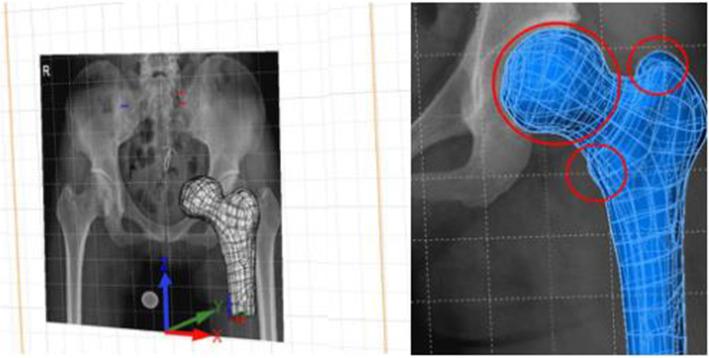

Five adult volunteers were recruited for an X-ray and CT examination in the same simulated bipedal standing position with a specialized patented device. We extracted these image data, calculated the 2D weight-bearing area on the X-ray image, reconstructed the 3D model of the proximal femur based on CT data, and registered them to realize the 2D weight-bearing area to 3D transformation as the quantified weight-bearing surface. One of the 3D models of the proximal femur was randomly selected for finite element analysis (FEA), and we defined three different loading surfaces and compared their FEA results.

A total of 10 weight-bearing surfaces in 5 volunteers were constructed, and they were mainly distributed on the dome and anterolateral of the femoral head with a crescent shape, in the range of 1218.63-1,871.06 mm. The results of FEA showed that stress magnitude and distribution in proximal femur FE models among three different loading conditions had significant differences, and the loading case with the quantized weight-bearing area was more in accordance with the physical phenomenon of the hip.